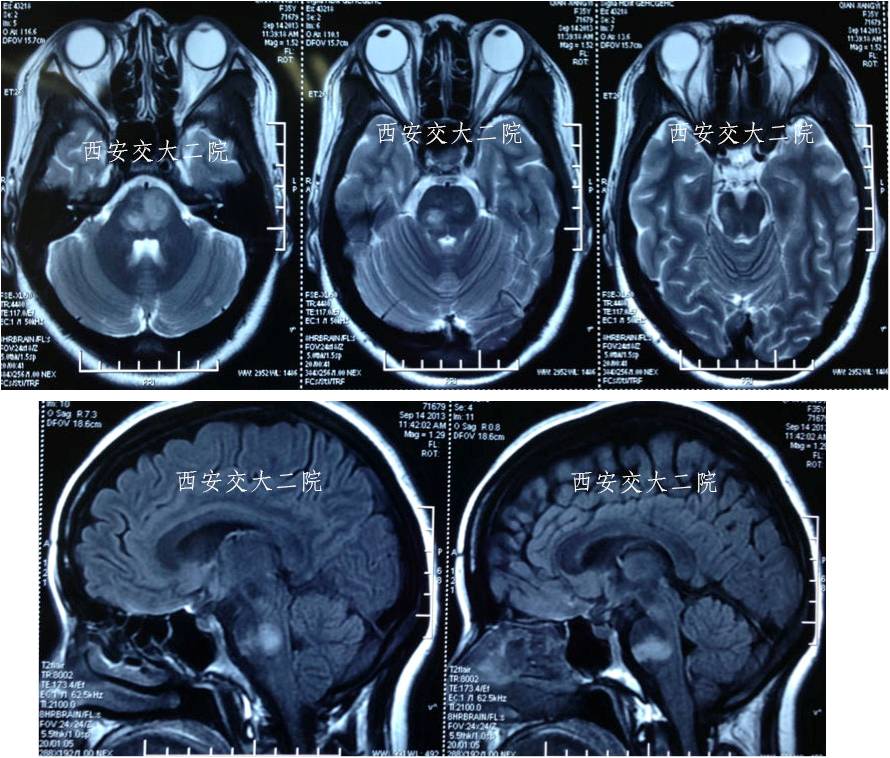

脑MR提示脑干大面积梗死

术后10天MR

术后10天MRA